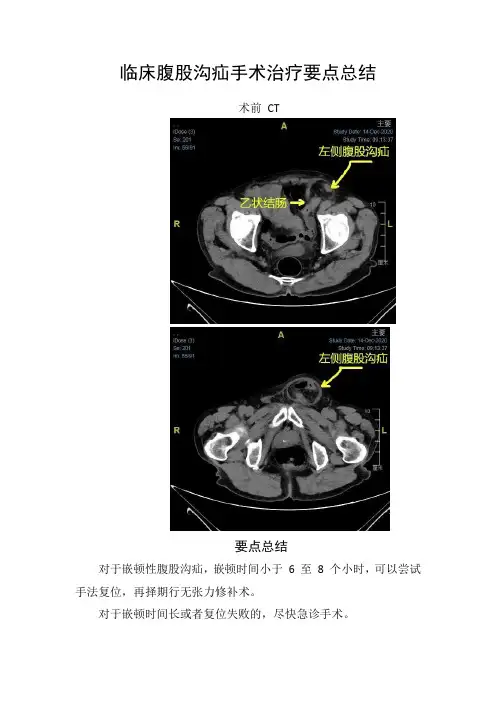

临床腹股沟疝手术治疗要点总结

术前CT

要点总结

对于嵌顿性腹股沟疝,嵌顿时间小于6 至8 个小时,可以尝试手法复位,再择期行无张力修补术。

对于嵌顿时间长或者复位失败的,尽快急诊手术。